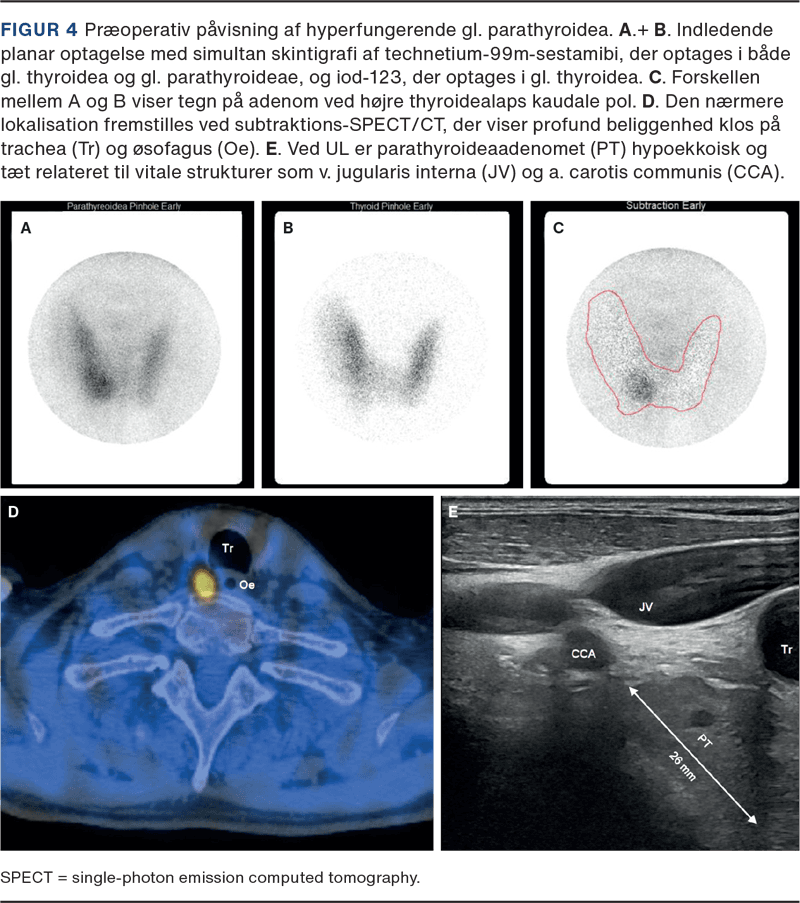

Modsat PET-skannere tillader gammakameraer simultan registrering af gammastråling med forskellige energier. Dette udnyttes ved dual isotopundersøgelser, hvor man sammenholder forskellige signaler i én optagelse og ved digital subtraktion fremstiller forskellene mellem dem. Det anvendes bl.a. ved lungeventilations- og perfusionsskintigrafi samt ved parathyroideaskintigrafi som vist i Figur 4.

Tomografiske (tredimensionelle) billeder bliver til efter rekonstruktion af rådata optaget hele vejen rundt om patienten og kræver højere aktivitetsmængder for et passende forhold mellem signal og støj. Ved hybridbilleddannelse kombineres en single-photon emission computed tomography (SPECT) med en CT, og resultatet er både en anatomisk lokalisation af sporstofoptagelsen og en dæmpningskorrektion, der skalerer signalerne efter vævsdybde. Et eksempel ses i Figur 3.